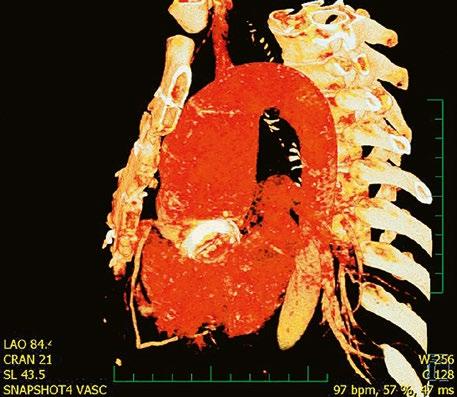

Supravalvární pulmonální stenóza a stenózy větví plicnice bývají součástí komplexních VSV (např. Fallotovy tetralogie) nebo syndromů (Williamsův syndrom, syndrom Noonanové, syndrom vrozené rubeoly, Alagillův syndrom aj.) (Obr. 45.39). Získané stenózy větví plicnice, ale i úplný uzávěr větve plicnice můžeme vidět po spojkových operacích podle BlalockaTaussigové (Obr. 45.40, Obr. 45.41). Pro zobrazení supravalvárních a periferních stenóz plicnice je optimální CT angiografie (Obr. 45.40, Obr. 45.41, Obr. 45.42, Obr. 45.43).

Obr. 45.40 CT angiografie, 8mm stenóza a deformace levé větve plicnice (šipka) po spojkové operaci podle BlalockaTaussigové v dětství LPA – levá větev plicnice, PA – kmen plicnice, RPA – pravá větev plicnice

Obr. 45.42 CT angiografie. Dilatace kmene plicnice (PA), periferní stenóza v oblasti bifurkace a odstupu pravé větve plicnice (RPA) označena šipkou, odstup levé větve plicnice (LPA) je také lehce zúžen.

Obr. 45.41 Uzávěr levé větve plicnice jako následek provedené spojky podle BlalockaTaussigové v dětství, CT angiografie

Obr. 45.43 CT angiografie, šipkou označena významná odstupová stenóza levé větve plicnice (LPA), lehčí stenóza odstupu pravé větve plicnice (RPA), kalcifikace v oblasti pulmonální chlopně